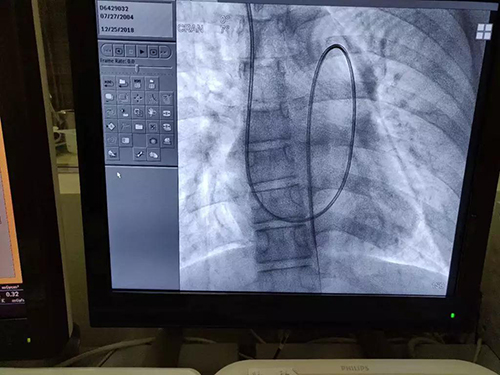

一例14岁动脉导管未闭合并肺动脉高压患者经颈静脉至降主动脉的漂浮导管路径